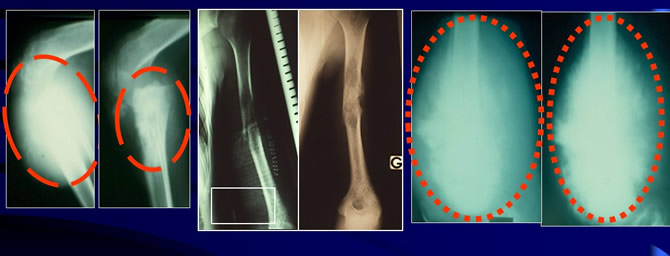

Response of OS after short preop HDMTX

4 to 5 weeks of individualized curses of HDMTX are enough even in case of fracture.

Preoperative chemotherapy can be dangerous

Too long preoperative chemotherapy may be dangerous if chemotherapy is not effective enough and may increase the risk of induction of chemoresistance and of metastases. All these patients died